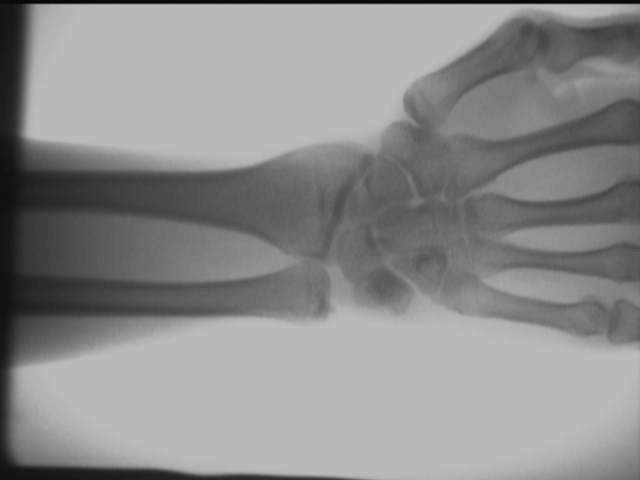

แผนภาพผลการทดสอบบนไซต์ของเครื่องตรวจจับเอ็กซ์เรย์ออร์โธพีดิกส์

ผลของข้อต่อข้อเท้ามือ

ผลการทดสอบข้างต้นได้มาที่ไซต์งานโดยใช้ AS-C200เครื่องเอ็กซ์เรย์แบบพกพา